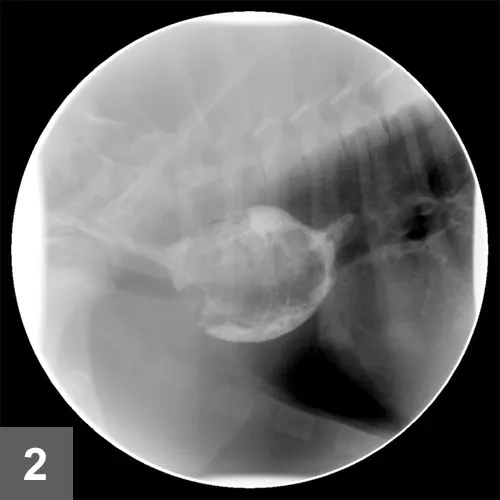

A barium esophagram identified esophageal narrowing at the base of the heart with dilation of the esophagus orad to the narrowing (Figure 2). Esophageal function distal to the constriction appeared normal.

FIGURE 2

Lateral view of contrast esophagram: Note the esophageal dilation cranial to the cardiac silhouette.

• Contrast esophagography using barium can document esophageal stricture at the level of the heart base.